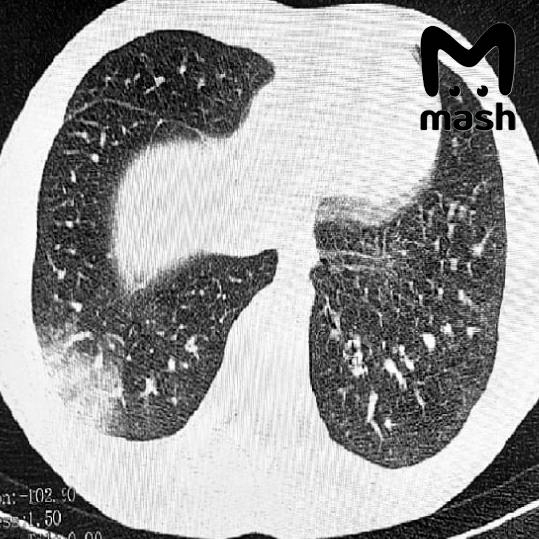

Почему курение вредно для легких? Большое количество свободных радикалов, содержащихся в продуктах сгорания табака, приводит к раздражению слизистой бронхолегочной системы и ее воспалению. О воспалительном процессе свидетельствуют частый кашель и отхаркивание, которые часто сопровождают курильщиков.

Также курение является одной из основных причин ХОБЛ (хронической обструктивной болезни легких). В перспективе это заболевание может привести к ограничению физической работоспособности и инвалидности.